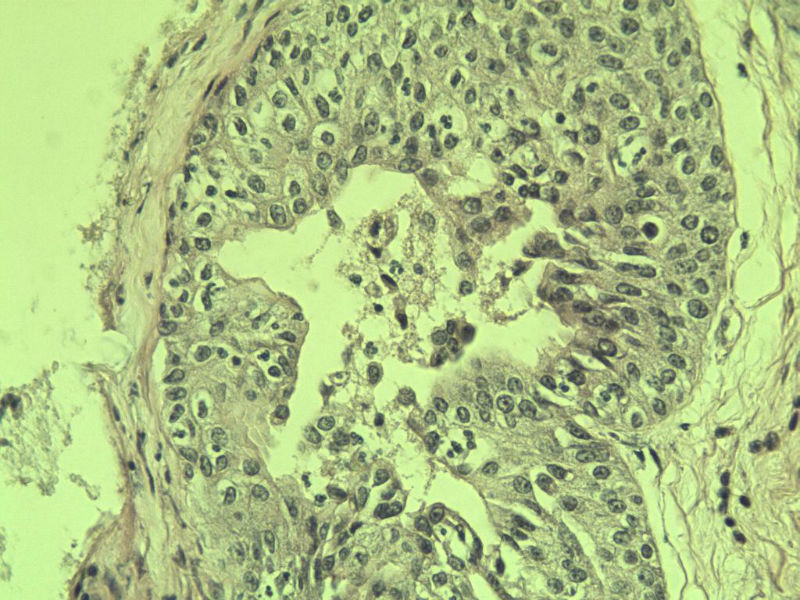

男 75岁 因排尿困难半年行前列腺切除术,体积 4 × 3 × 2.5 cm3,切面灰白,实性,质韧。请各位老师看看 有问题没? 谢谢了!

高级别上皮内瘤变,建议免疫组化:P63、34BE12、P504S

前列腺增生症伴鳞化

良性前列腺增生伴尿路上皮化生

前列腺增生伴尿路上皮鳞化及Brown巢形成,未见恶性。